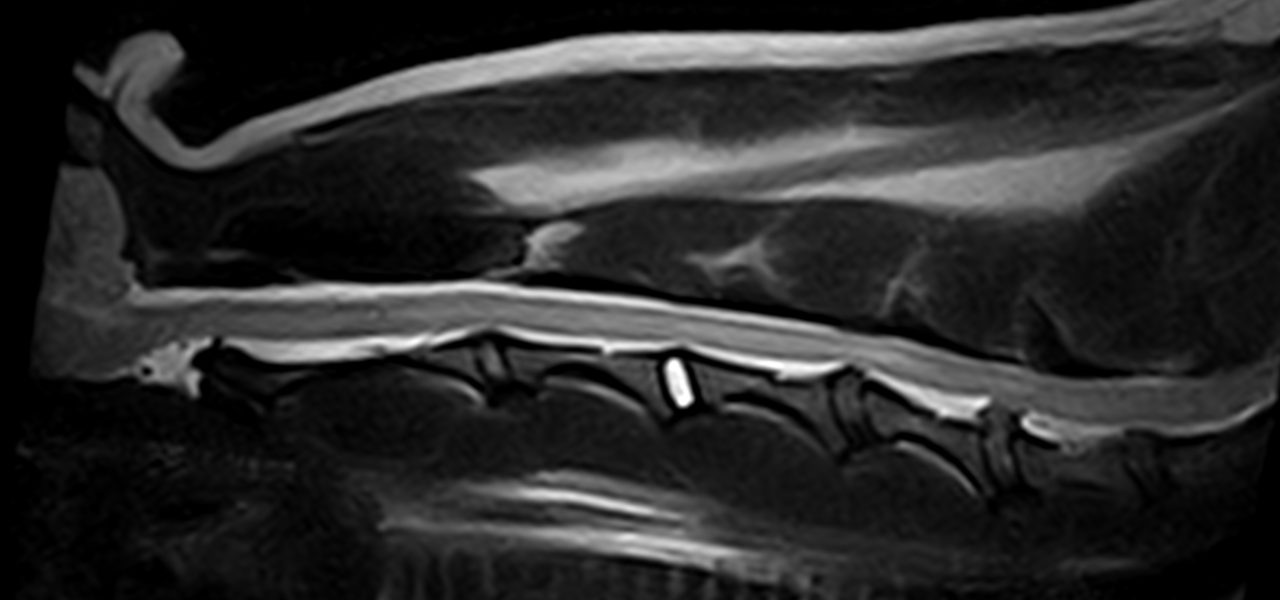

10歳のイタグレさんが四肢不全麻痺になっているので、精査希望で来院されました。MRIではC4~C5,C5~C6、の中程度のIVDDが確認されました。今回は経皮的椎間板レーザー除圧術(PLDD)により対応しました。ニードルを外科イメ誘導下で椎間板に穿刺し、穿刺部位はCTで確認し、問題なければそのままレーザーファイバーを挿入し、蒸散を行います。この手技は今まで外科的に適応されなかった多発性の椎間板ヘルニアにも低侵襲アプローチが可能となります。しかし、即効性はないため鎮痛剤を使いながら経過観察を行います。